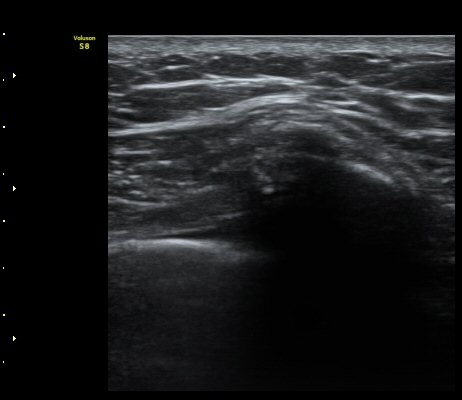

ÇÑ´Þ ÈÄ ÃßÀû°Ë»ç

Á¾´Ü¸é°Ë»ç¿¡¼­ °¡°ñ Çü¼ºÀÌ °üÂûµÊ(formation of callus)   »çÁø 3

°¥ºñ»À Ⱦ´Ü¸é°Ë»ç¿¡¼­ °¡°ñ Çü¼ºÀÌ °üÂûµÊ(formation of callus)  »çÁø 4